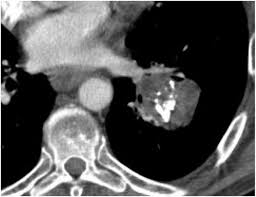

A description of popcorn calcification—meaning images that look like popcorn on a ct. Eccrine angiokeratomatous hamartoma combined with solitary angiokeratoma or verrucous venous malformation: Residents and fellows contest rules | international ophthalmologists contest rules. Endobronchial hamartoma resected by rigid bronchoscope. Report of two cases and comprehensive review of the literature.

A large hamartoma of the spleen. Multiple hamartomas throughout the body occur in cowden's disease. A description of popcorn calcification—meaning images that look like popcorn on a ct. Endobronchial hamartoma resected by rigid bronchoscope. A mass resembling a tumor that represents anomalous development of tissue natural to a part or organ rather than a true tumor. Most isolated hamartomas are benign but in cowden's disease there is a risk that one or more may undergo malignant change.4. High magnification shows the 3 components of fhi. Report of two cases and comprehensive review of the literature.

Hamartoma is a benign (not cancer) growth made up of an abnormal mixture of cells and tissues normally found in the area of the body where the a lesion first described by german pathologist eugen albrecht in 1904, hamartomas are generally benign tumors that may occur in the lungs, skin. A description of popcorn calcification—meaning images that look like popcorn on a ct. The hamartoma can occur in almost any organ and is usually asymptomatic. High magnification shows the 3 components of fhi. In radiology, hamartomas often mimic malignancy. Jump to navigation jump to search. Is that hamartoma is (pathology) a benign mass of disorganized tissue while teratoma is (pathology) a benign or malignant tumour, especially of the gonads, that arises from germ cells and consists of different types of tissue such as skin, hair, or muscle. When located on the skin, especially the face or neck, they can be extremely disfiguring, as.

A description of popcorn calcification—meaning images that look like popcorn on a ct. High magnification shows the 3 components of fhi. A hamartoma is a focal malformation that resembles a neoplasm in the tissue of its origin. The hamartoma is the dark circular object on the left that dominates the image. A large hamartoma of the spleen.